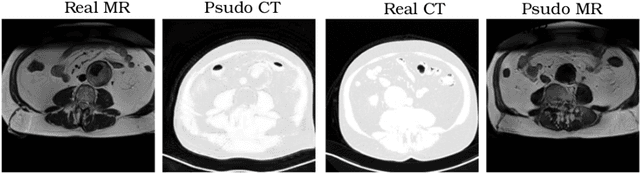

Abstract:Typically, a medical image offers spatial information on the anatomy (and pathology) modulated by imaging specific characteristics. Many imaging modalities including Magnetic Resonance Imaging (MRI) and Computed Tomography (CT) can be interpreted in this way. We can venture further and consider that a medical image naturally factors into some spatial factors depicting anatomy and factors that denote the imaging characteristics. Here, we explicitly learn this decomposed (factorised) representation of imaging data, focusing in particular on cardiac images. We propose Spatial Decomposition Network (SDNet), which factorises 2D medical images into spatial anatomical factors and non-spatial imaging factors. We demonstrate that this high-level representation is ideally suited for several medical image analysis tasks, such as semi-supervised segmentation, multi-task segmentation and regression, and image-to-image synthesis. Specifically, we show that our model can match the performance of fully supervised segmentation models, using only a fraction of the labelled images. Critically, we show that our factorised representation also benefits from supervision obtained either when we use auxiliary tasks to train the model in a multi-task setting (e.g. regressing to known cardiac indices), or when aggregating multimodal data from different sources (e.g. pooling together MRI and CT data). To explore the properties of the learned factorisation, we perform latent-space arithmetic and show that we can synthesise CT from MR and vice versa, by swapping the modality factors. We also demonstrate that the factor holding image specific information can be used to predict the input modality with high accuracy.

Abstract:Recently, the cycle-consistent generative adversarial networks (CycleGAN) has been widely used for synthesis of multi-domain medical images. The domain-specific nonlinear deformations captured by CycleGAN make the synthesized images difficult to be used for some applications, for example, generating pseudo-CT for PET-MR attenuation correction. This paper presents a deformation-invariant CycleGAN (DicycleGAN) method using deformable convolutional layers and new cycle-consistency losses. Its robustness dealing with data that suffer from domain-specific nonlinear deformations has been evaluated through comparison experiments performed on a multi-sequence brain MR dataset and a multi-modality abdominal dataset. Our method has displayed its ability to generate synthesized data that is aligned with the source while maintaining a proper quality of signal compared to CycleGAN-generated data. The proposed model also obtained comparable performance with CycleGAN when data from the source and target domains are alignable through simple affine transformations.